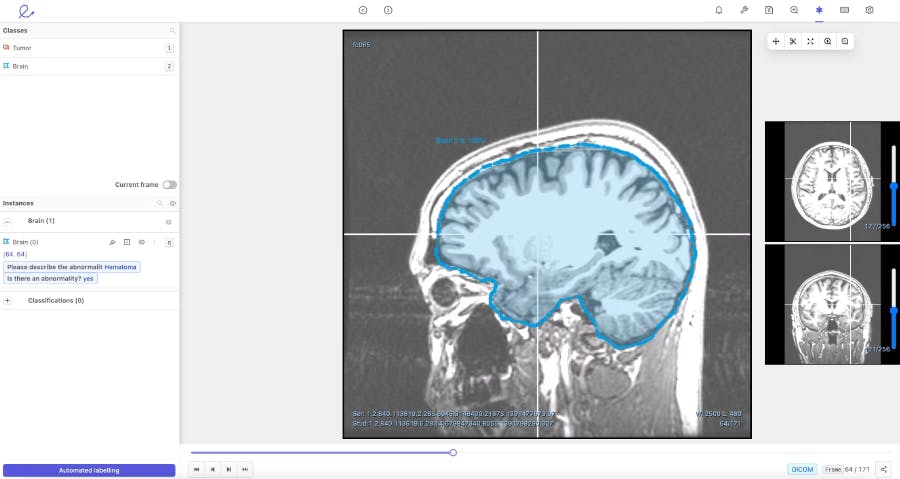

To facilitate the review process and help doctors annotate more efficiently, Encord developed our DICOM annotation tool– the first comprehensive annotation tool with native 3D annotation capabilities designed for medical AI. It is built to handle multiple medical imaging modalities, including CT, X-ray, and MRI. Our DICOM tool combines an approach of training and running automated models, with human supervision to review and refine labels. When it comes to ground truth review, the tool improves efficiency, reduces costs, and increases accuracy– making it an asset for time-pressed doctors and cost conscious hospitals.

When building our DICOM 3D-image annotation tool we consulted with physicians in King’s College, academics at Stanford, and ML experts at AI radiology companies building these types of medical vision models. As a result, we knew that our platform needed to have a flexible interface that enabled collaboration between clinical teams and data science teams. It had to be able to support multiple reviews, facilitate a consensus across different opinions, and perform quality assessments to check the ground truth of the algorithm automating data labelling.

We developed our DICOM annotation tool to augment and replace the manual labelling process that makes AI development expensive, time consuming, and difficult to scale. Currently, most AI development relies on outsourcing data to human labellers, including clinicians. The human error that arises during this process results in doctors having to waste time reviewing and correcting labels. With the DICOM image annotation tool, we hope to save physicians valuable time by giving them the right tools and by reducing their burden of manual labelling.

It’s an upstream approach, but creating our DICOM image annotation tool is our way of contributing to early cancer detection and prevention. Organisations that use the tool can increase the speed at which computer vision models can enter production and become viable for use in a medical environment.